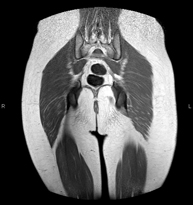

Exploración para el estudio de lesiones en tendones, músculos y articulaciones coxofemorales. Permite identificar de forma precoz la artrosis de cadera. Resulta muy útil para detectar las bursitis y la osteopatía dinámica del pubis, frecuente en deportistas. Tiene una duración aproximada de 20 minutos. No emplea radiación ionizante. - RM Sacroilíacas

Estudio específicamente diseñado para valorar estas articulaciones y su inflamación en los pacientes que sufren Espondilitis Anquilosante. También resulta de utilidad en pacientes con traumatismos y posibles fracturas del sacro y el cóccix. Tiene una duración aproximada de 16 minutos. No emplea radiación ionizante. - RM Glúteos

Exploración para el estudio de la musculatura y de los tendones que se originan a este nivel, como los tendones isquiotibiales, frecuentemente lesionados en deportistas. Tiene una duración aproximada de 16 minutos. No emplea radiación ionizante. - RM Muslo